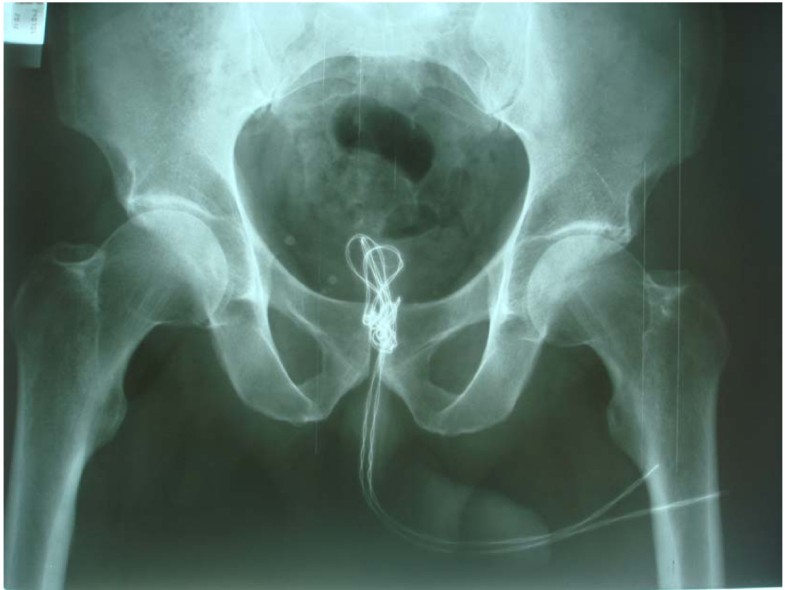

Electrical Wire As A Foreign Body In A Male Urethra: A Case Report

Electrical wire as a foreign body in a male urethra: a case report jmedicalcasereports.biomedcentral.com

urethra bladder ureter urethral meatus